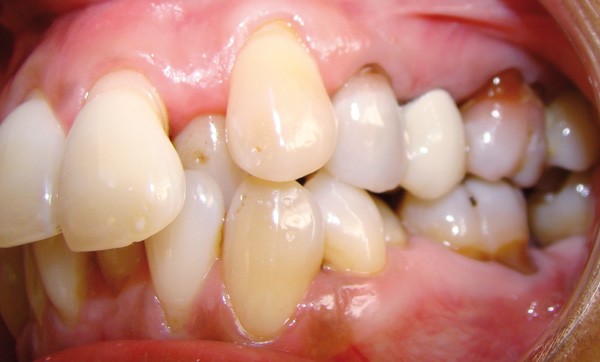

Bien souvent, dans les formes sévères, la diminution du boîtier osseux entraîne la migration et le déplacement de dents et notamment dans le secteur antérieur. Ces migrations ont un aspect disgracieux qui amène bon nombre de patients à consulter un orthodontiste pour corriger ces malpositions et retrouver à la fois une esthétique du sourire plus agréable et une fonction masticatrice plus efficace. Cependant, l’origine de ces migrations tient à l’inflammation du parodonte se traduisant par une plus grande laxité ligamentaire et une destruction du boîtier osseux. Dans certains cas, une surcharge occlusale aggrave encore le déplacement. Le traitement de l’inflammation par une thérapeutique initiale parodontale diminue la migration mais souvent, ne suffit pas à retrouver un positionnement correct (fig. 1). Il est alors nécessaire de mettre en œuvre une prise en charge orthodontique.